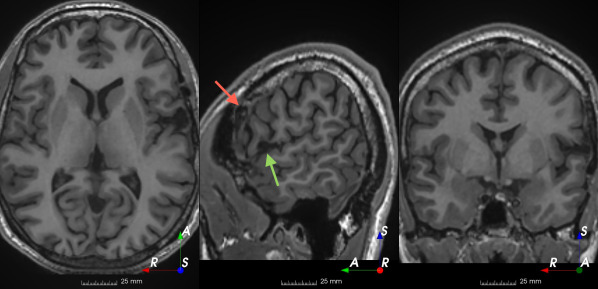

Refer to caption

(a)

(b)

(c)

(d)

(e)

(f)

(g)

(h)

Figure 6: Examples of challenging images for cavity segmentation. (a) Small frontal lesionectomy surrounded by hypointense white matter (b) Brain shift after contralateral temporal lobectomy (not shown) (c) Small frontal lesionectomy near the Sylvian fissure (d) Lack of boundaries between oedema and resection cavity (e) Possible blood clot within the cavity (f) Brain shift, oedema and resection cavity (g) Arachnoid cyst and resection cavity (h) Cerebellar degeneration. Green annotations represent areas that correspond to resection cavities; red annotations represent areas that do not.

Predictions errors are mostly due to 1) resection of size comparable to sulci (Fig. 6a), 2) unanticipated intensities, such as those caused by the presence of blood clots in the cavity (Fig. 6b), 3) brain shift (Fig. 6c) and 4) white matter hypointensities (Fig. 6e). Further work will involve using different internal and external cavity textures, carefully sampling the resection volume, simulating brain shift using biomechanical models, and quantifying epistemic and aleatoric segmentation uncertainty to better assess model performance [24].